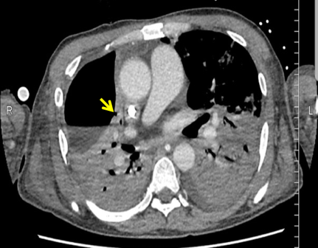

ภาพถ่ายรังสีคอมพิวเตอร์ (chest computed tomography) มักพบลักษณะโพรงน้ำและอากาศในช่องเยื่อหุ้มปอด (hydropneumothorax) โดยอาจพบลักษณะของฟองอากาศที่เกิดขึ้นภายในร่วมด้วย และพบเงาฝ้าเกิดขึ้นในบริเวณอื่น ทั้งนี้อาจะพบตำแหน่งรูรั่วที่เป็นทางเชื่อมระหว่างแขนงหลอดลมกับช่องเยื่อหุ้มปอดได้ ดังรูปที่ 2 โดยโอกาสที่จะตรวจพบรูรั่วดังกล่าวนั้นมีประมาณร้อยละ 5013